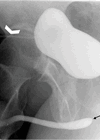

Male urethrograms

An ascending urethrogram is the best initial radiographic technique to image a male patient’s urethra and is indicated for strictures, fistulae, trauma and urethral obstruction [1]. It is quick and straightforward to perform and is performed using an 8Fr Foley...